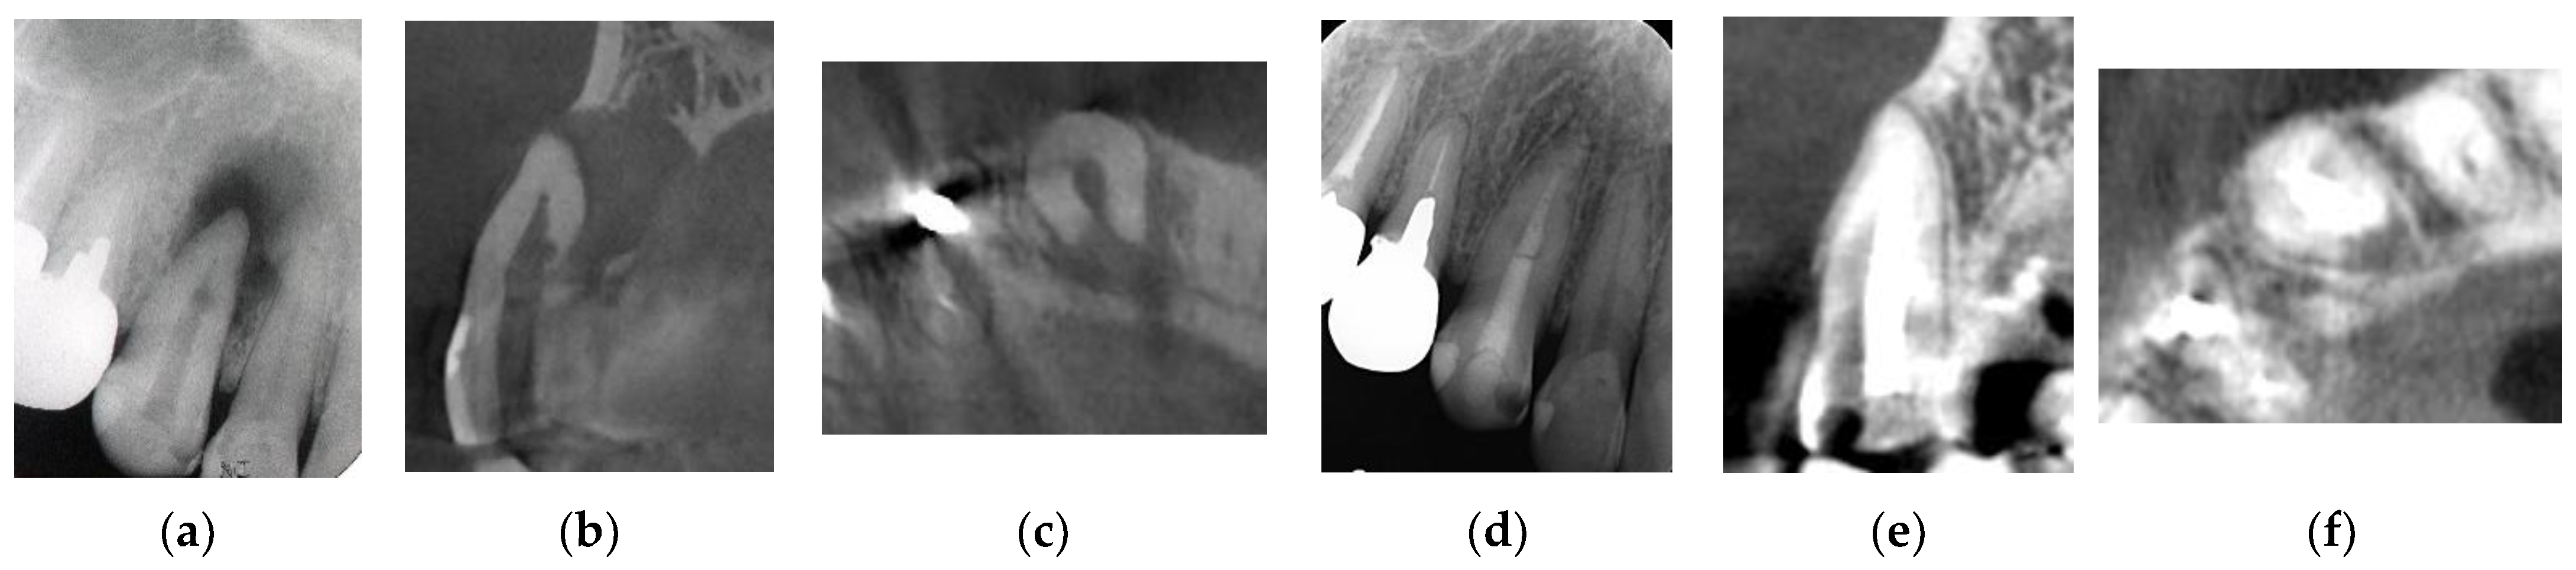

Figure 2. Clinical case 1. Male, age 43 yrs. (a) Preoperative periapical radiograph of the right maxillary canine, with the “bone” defect presenting as a radiolucent area in both the middle of the root and the apical lesion. (b,c) Preoperative CBCT showing a radiolucent lesion on the periapical and palatal areas. This patient underwent endodontic treatment with MTA under microscopy. (d) Follow-up periapical radiograph 4 years later. (e,f) Follow-up CBCT 4 years later, showing filling of the root canal and healing.

Figure 5. Clinical case 4. Male, age 34 yrs. (a) Intraoral view of the upper left incisor at baseline. (b) Preoperative periapical radiographs of the upper left incisor, with the “bone” defect presenting as a radiolucent area in the apical lesion. (c) Preoperative CBCT showing a radiolucent lesion on the labial, periapical, and palatal areas. (d) Intraoral view 2 years after treatment. (e) Follow-up periapical radiograph 2 years after treatment. (f) Follow-up CBCT 2 years after treatment, showing root canal filling and healing.